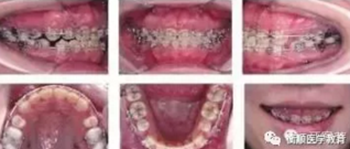

圖4 種植體支抗關(guān)閉拔牙間隙,同時行上頜前、后牙垂直向控制

矯治結(jié)果